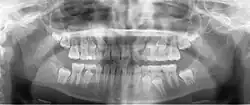

A dental panoramic radiograph, showing the maxilla and mandible, all the teeth including the "wisdom teeth," the frontal and maxillary sinuses, the nasal cavity and the temporomandibular joint and other near by head and neck anatomy.

A panoramic radiograph is a panoramic scanning dental X-ray of the upper and lower jaw. It shows a two-dimensional view of a half-circle from ear to ear. Panoramic radiography is a form of focal plane tomography; thus, images of multiple planes are taken to make up the composite panoramic image, where the maxilla and mandible are in the focal trough and the structures that are superficial and deep to the trough are blurred.